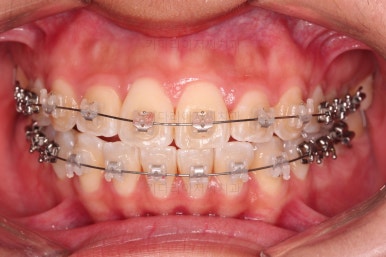

이번 환자분이 선택한 장치는 엠파워 클리어라고 하는 자가결찰 세라믹 장치입니다.

흔히들 아시는 클리피씨 장치와 동일한 종류의 장치인데, 제조국이 일본(클리피)이냐 미국(엠파워)이냐의 차이가 있습니다.

부산연산역치아교정 치료한지 5개월째 사진입니다.

빠른 시일 내에 가지런하게 되었고, 사랑니도 발치를 했으며, 통째로 뒤로 밀어주기 위한 미니스크류 세팅도 끝난 상황입니다.

주기적으로 내원하면서 뒤로 당기는 힘 조절만 해주면 되는 단계입니다.